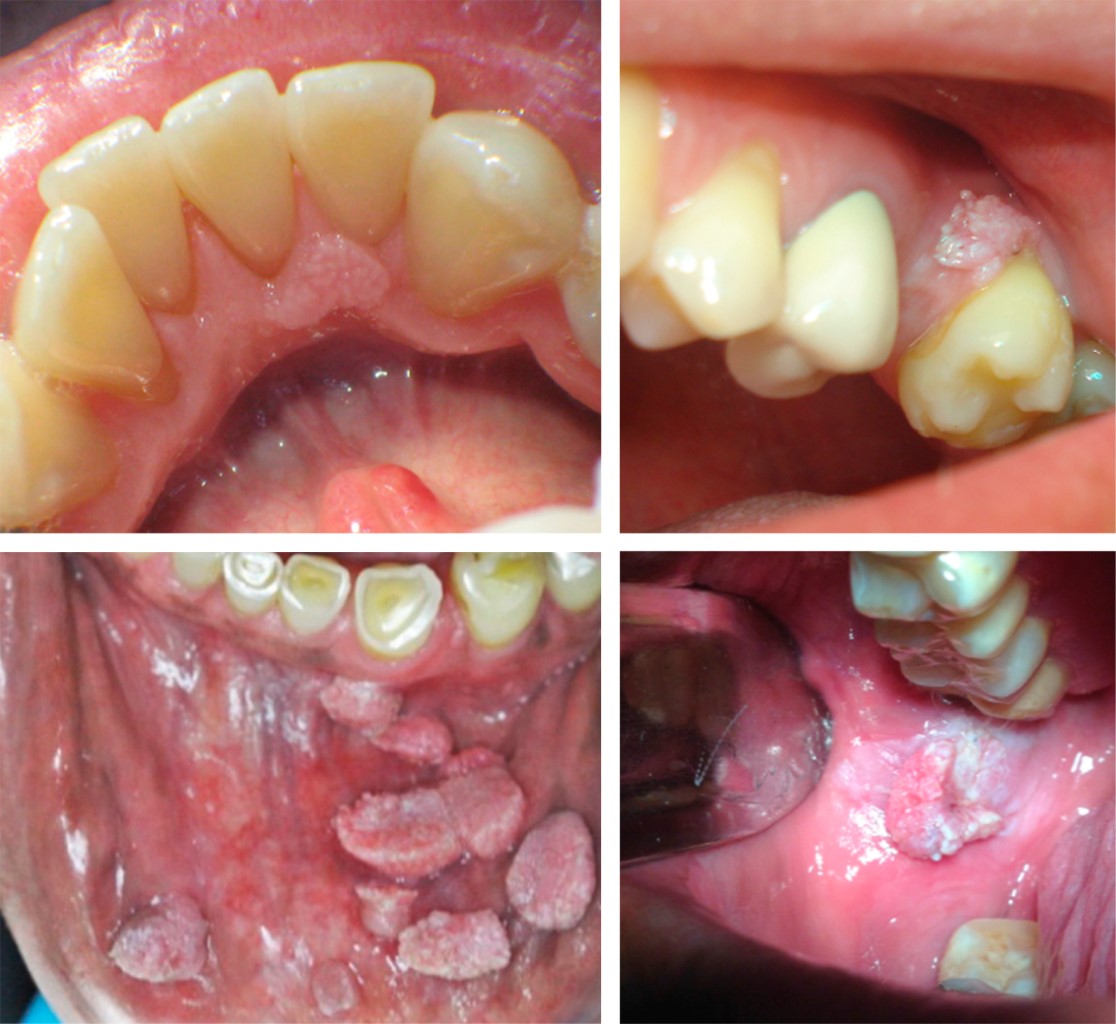

Condyloma acuminatum in the oral cavity: review of the literature

Condyloma acuminatum (CA) is a lesion and a sexually transmitted disease transmitted by the human papillomavirus (HPV) subtypes 6 and 11 characterized by its exophytic papillomatous cauliflower-like appearance. It is most frequently observed in the anogenital region, however, it can also be found in the oral mucosa. The definitive diagnosis is clinicopathologic and is made by histopathologic study of the lesion and clinical history. The treatment is surgical removal of the lesion by means of scalpel, laser, cryotherapy, among others. Although in some cases the use of immunomodulators, such as imiquimod, is the treatment of choice.

Figure 1

Figure 2

Figure 3